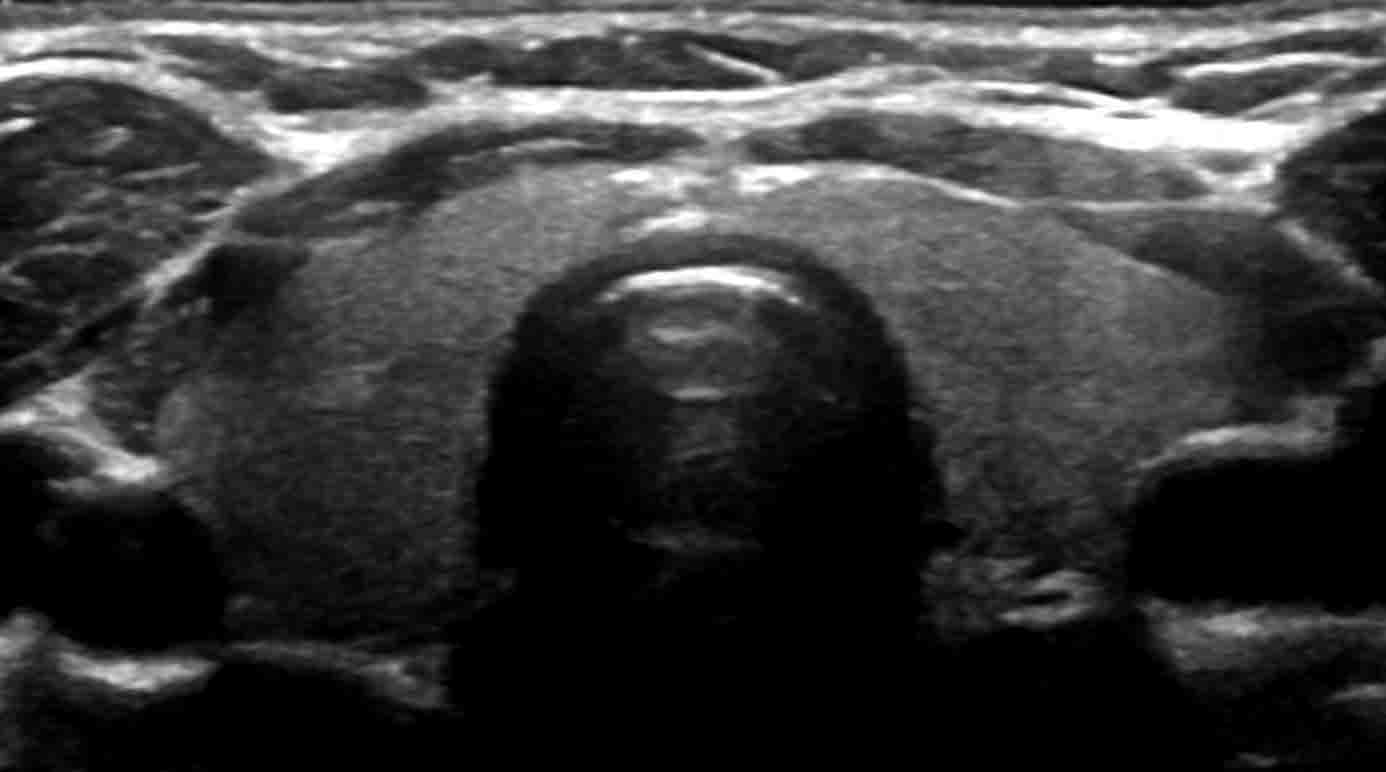

Thyroid

Our Thyroid ultrasound application describes the overall dimensions and descriptors of the thyroid, a table of nodules with dimensions imported from the modality with additional descriptors which calculates the TI-RADS score. A thyroid diagram can easily communicate nodule location to the ordering physician and the report clearly outlines next steps.

- Thyroid Ultrasound